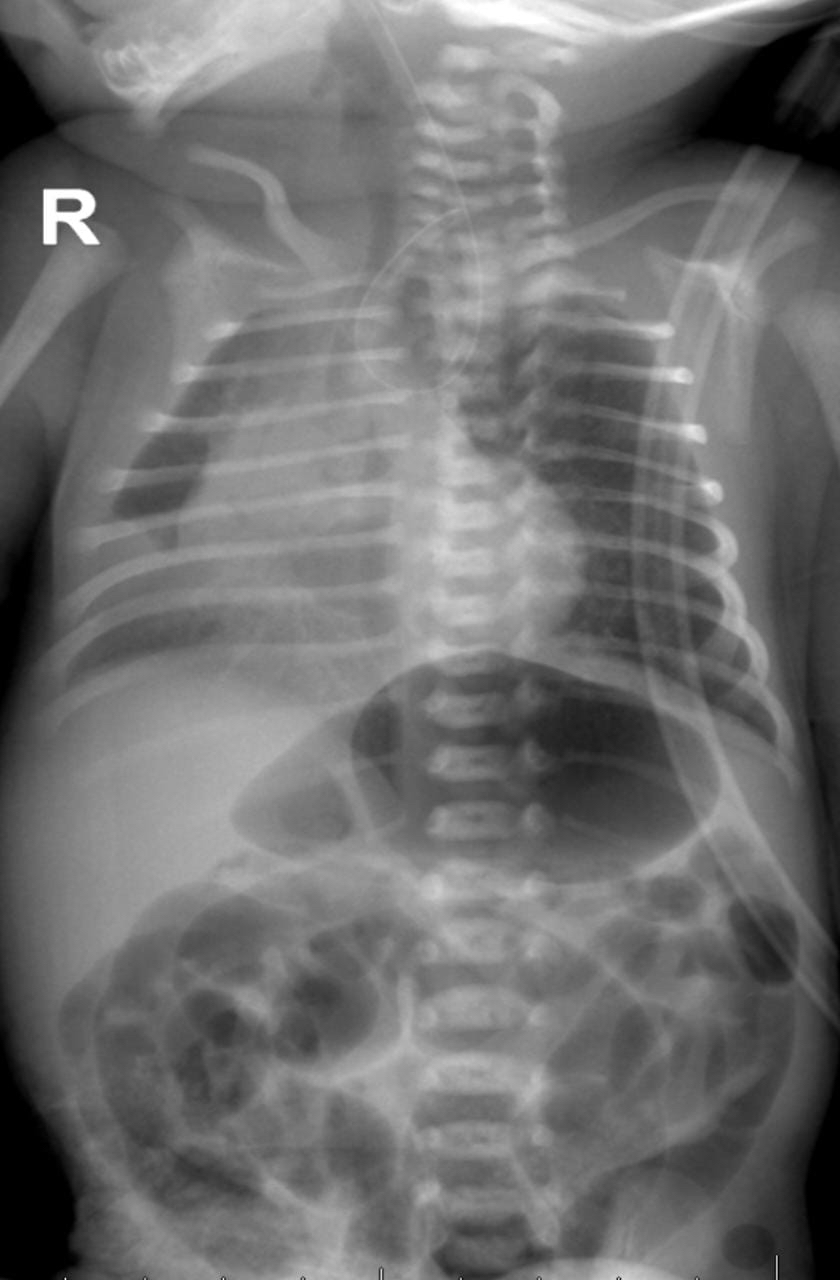

نجح فريق طبي في قسم جراحة الأطفال بمستشفى القطيف المركزي، أحد مكونات تجمع الشرقية الصحي، في إصلاح عيب خلقي نادر، يتمثل في ”رتق المريء مع ناسور رغامي مريئي“ لطفلة حديثة الولادة ”خديج“ تزن 1,7 كيلوغرام وتبلغ من العمر 5 أيام.

ويعد رتق المري عاهة جسدية خلقية تتمثل بعدم نمو المريء بشكل سليم، ويكون جزء المريء العلوي مسدودا وجزؤه السفلي في أغلب الأحيان، مرتبطا مباشرة بالقصبة الهوائية. وتمثل نسبة انتشار ظاهرة رتق المريء هي «1» لكل «4000» مولود.